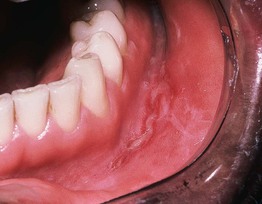

Fig. 59.15 Crohn's disease. Linear ulceration of the mandibular vestibule is the classic oral manifestation of this disease. Courtesy, Carl M. Allen, MD, and Charles Camisa, MD.

Fig. 59.16 Wegener's granulomatosis – strawberry gums. The affected areas of the gingiva are red-purple, micropapular, and friable, with a resemblance to ripe strawberries. Courtesy, Carl M. Allen, MD, and Charles Camisa, MD.